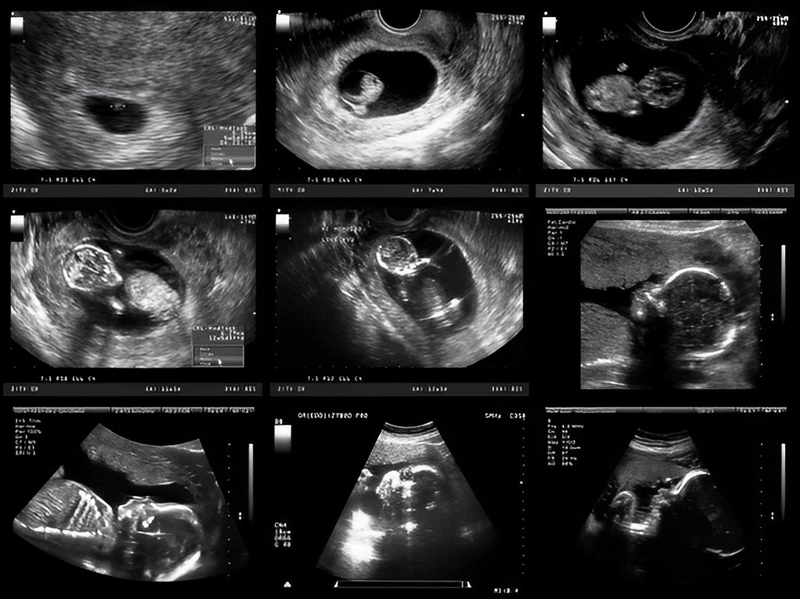

Nhau thai được ví như một sợi dây quan trọng kết nối mẹ và bé trong thai kỳ. Nhau thai có hình tròn, màu đỏ, nặng tới 0.9 kg, hình thành từ lúc phôi thai bám vào thành tử cung. Cùng lúc đó, các tế bào trong phôi thai sẽ chia thành hai nhóm, bao gồm nhau thai và thai nhi. Sau đó vài ngày, nhau thai sẽ bám vào lớp nội mạc tử cung để cung cấp dinh dưỡng cho thai nhi. Từ tuần thứ 10 của thai kỳ, nhau thai có thể quan sát được thông qua siêu âm.

Khi nhau thai bám mặt sau, nó có thể gây ra rủi ro cho thai nhi, bao gồm khả năng bị rối loạn chức năng của các cơ quan và tổn thương vùng bụng. Việc xác định xem nhau thai có bám mặt sau hay không thông qua siêu âm là rất quan trọng để theo dõi sự phát triển của thai nhi, từ đó đưa ra quyết định điều trị phù hợp.